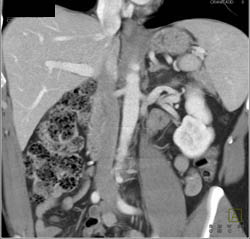

3D Mapping of Renal Donor- 2 Right Renal Arteries With Prehilar Branching